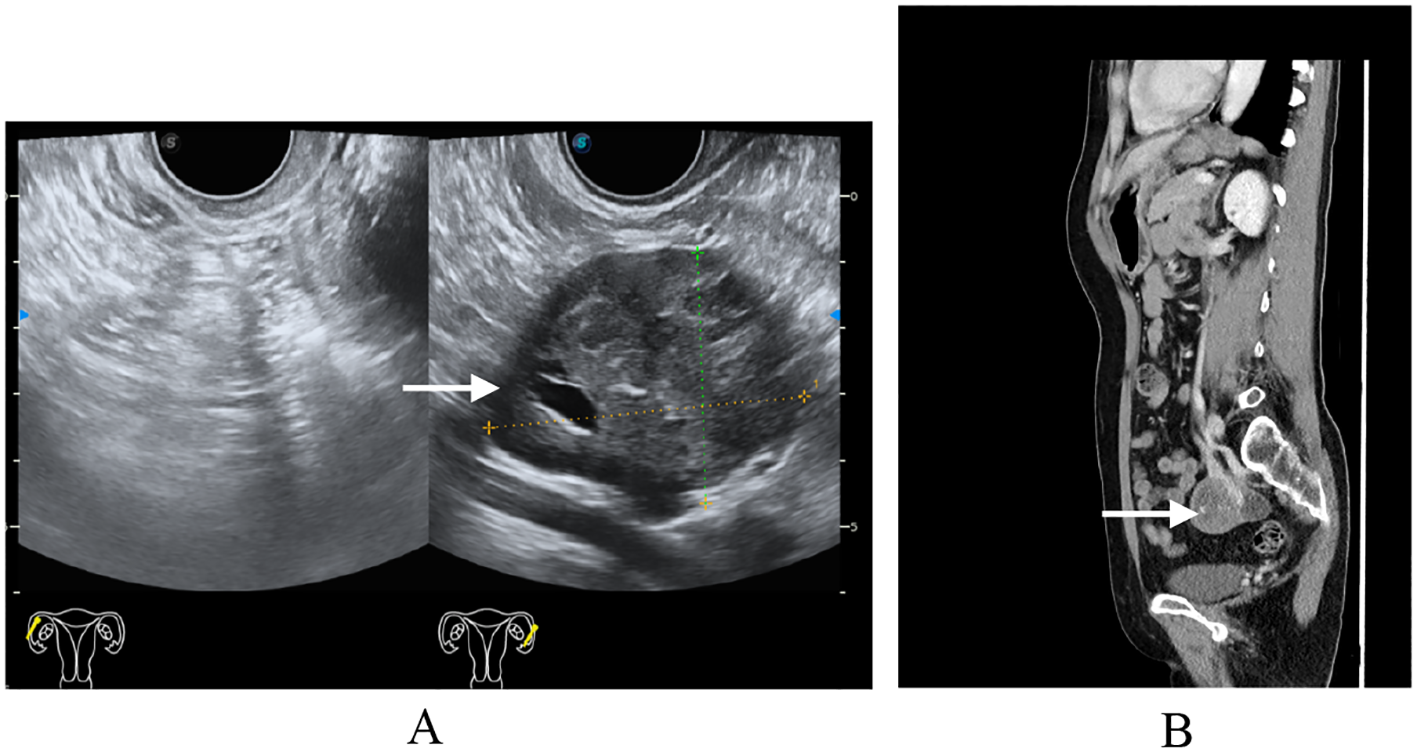

Definitive pathology confirmed Wolffian tumor (ICD code: 9110/1), which measured 5.2 cm in maximal diameter. The tumor was confined to the left ovarian parenchyma without capsular invasion, with negative margins, and without involvement of adjacent structures. The resected tumor specimen was thoroughly examined. Macroscopically, the tumor appeared well circumscribed, with a solid and partially cystic cut surface. Microscopically, the tumor exhibited a mixed growth pattern, including solid, tubular, and sieve-like structures. The tumor cells were uniform and bland, with scant cytoplasm and round to oval nuclei. Focal areas showed hyalinized vascular stroma and intraluminal eosinophilic secretions. Immunohistochemistry showed the following: FOXL2 (+++, strongly positive), calretinin (++), SF-1 (++), α-inhibin (++), vimentin (++), CD10 (focal luminal positivity), and AR (+). On the other hand, ER, PR, EMA, GATA3, and TTF-1 were negative. The Ki-67 proliferation index was approximately 1% (Figure 2), indicating low cellular activity. These features supported diagnosis as a rare adnexal tumor of borderline malignant potential. Multidisciplinary consensus recommended no adjuvant therapy. A rigorous surveillance protocol was suggested, including quarterly gynecological exams, tumor marker assessments, and imaging studies. At the 12-month follow-up, the patient remained asymptomatic with normal tumor markers and no evidence of recurrence on pelvic ultrasound/CT, achieving 1-year progression-free survival (PFS). Long-term monitoring continues.

Figure 2. Immunohistochemistry of Wolffian tumor. Immunohistochemical stains (×200) for FOXL2+ (A) α-inhibin+ (B) calretinin+ (C) and epithelial membrane antigen− (D).